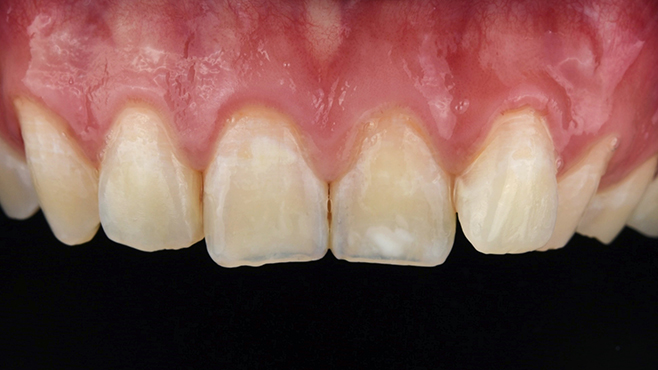

실제 치료 사례

수많은 환자들이 고민 끝에 선택한 치료,

그리고 그 후의 놀라운 변화

- ※ 위 임상사진은 365서울원탑치과에서 진료를 시작하고 마친 동일한 환자의 사진입니다.

- ※ 위 임상사진은 동일한 장소에서 동일한 조건으로 촬영되었으며, 사진에 대한 별도의 조작이 처리되지 않았습니다.

- ※ 수술 및 치료 과정에서 부작용이 발생할 수 있으므로 의료진과의 충분한 상담과 신중한 판단이 요구됩니다.